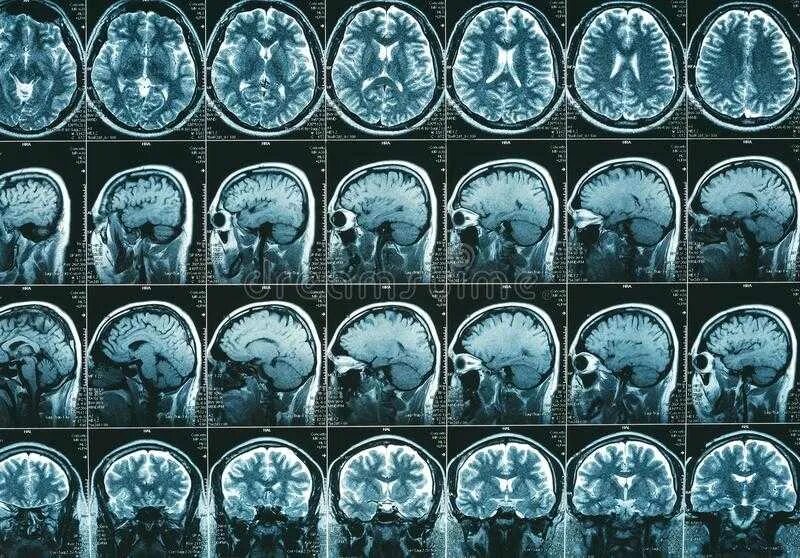

Можно ли делать мрт после операции